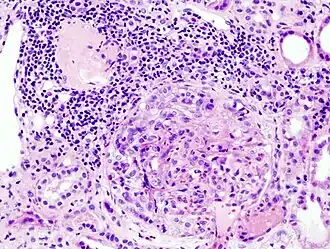

| Histopatologia de glomerulonefrite com formação Crescente causada por anticorpos antineutrófilos citoplasmáticos (ANCA). | |

Glomerulonefrite rapidamente progressiva (GNRP) ou glomerulonefrite crescêntica é uma doença renal caracterizada pelo declínio de mais de 50% da filtração glomerular em menos de 3 meses. Gera uma insuficiência renal aguda irreversível e potencialmente fatal. Afeta quatro em cada um milhão de habitantes, sendo mais comum entre mulheres e idosos.[1]

Após identificar o rápido compromisso da função renal com um exame de creatinina, ureia, albumina e hemácias no sangue e na urina é recomendado uma ultrassonografia dos rins para ver se os rins estão aumentados, biópsia renal para ver se há padrão de "lua crescente" nos glomérulos (visível em até 75% dos casos) e um exame de autoanticorpos (ANA, ANCA e Anti-GBM).[3]